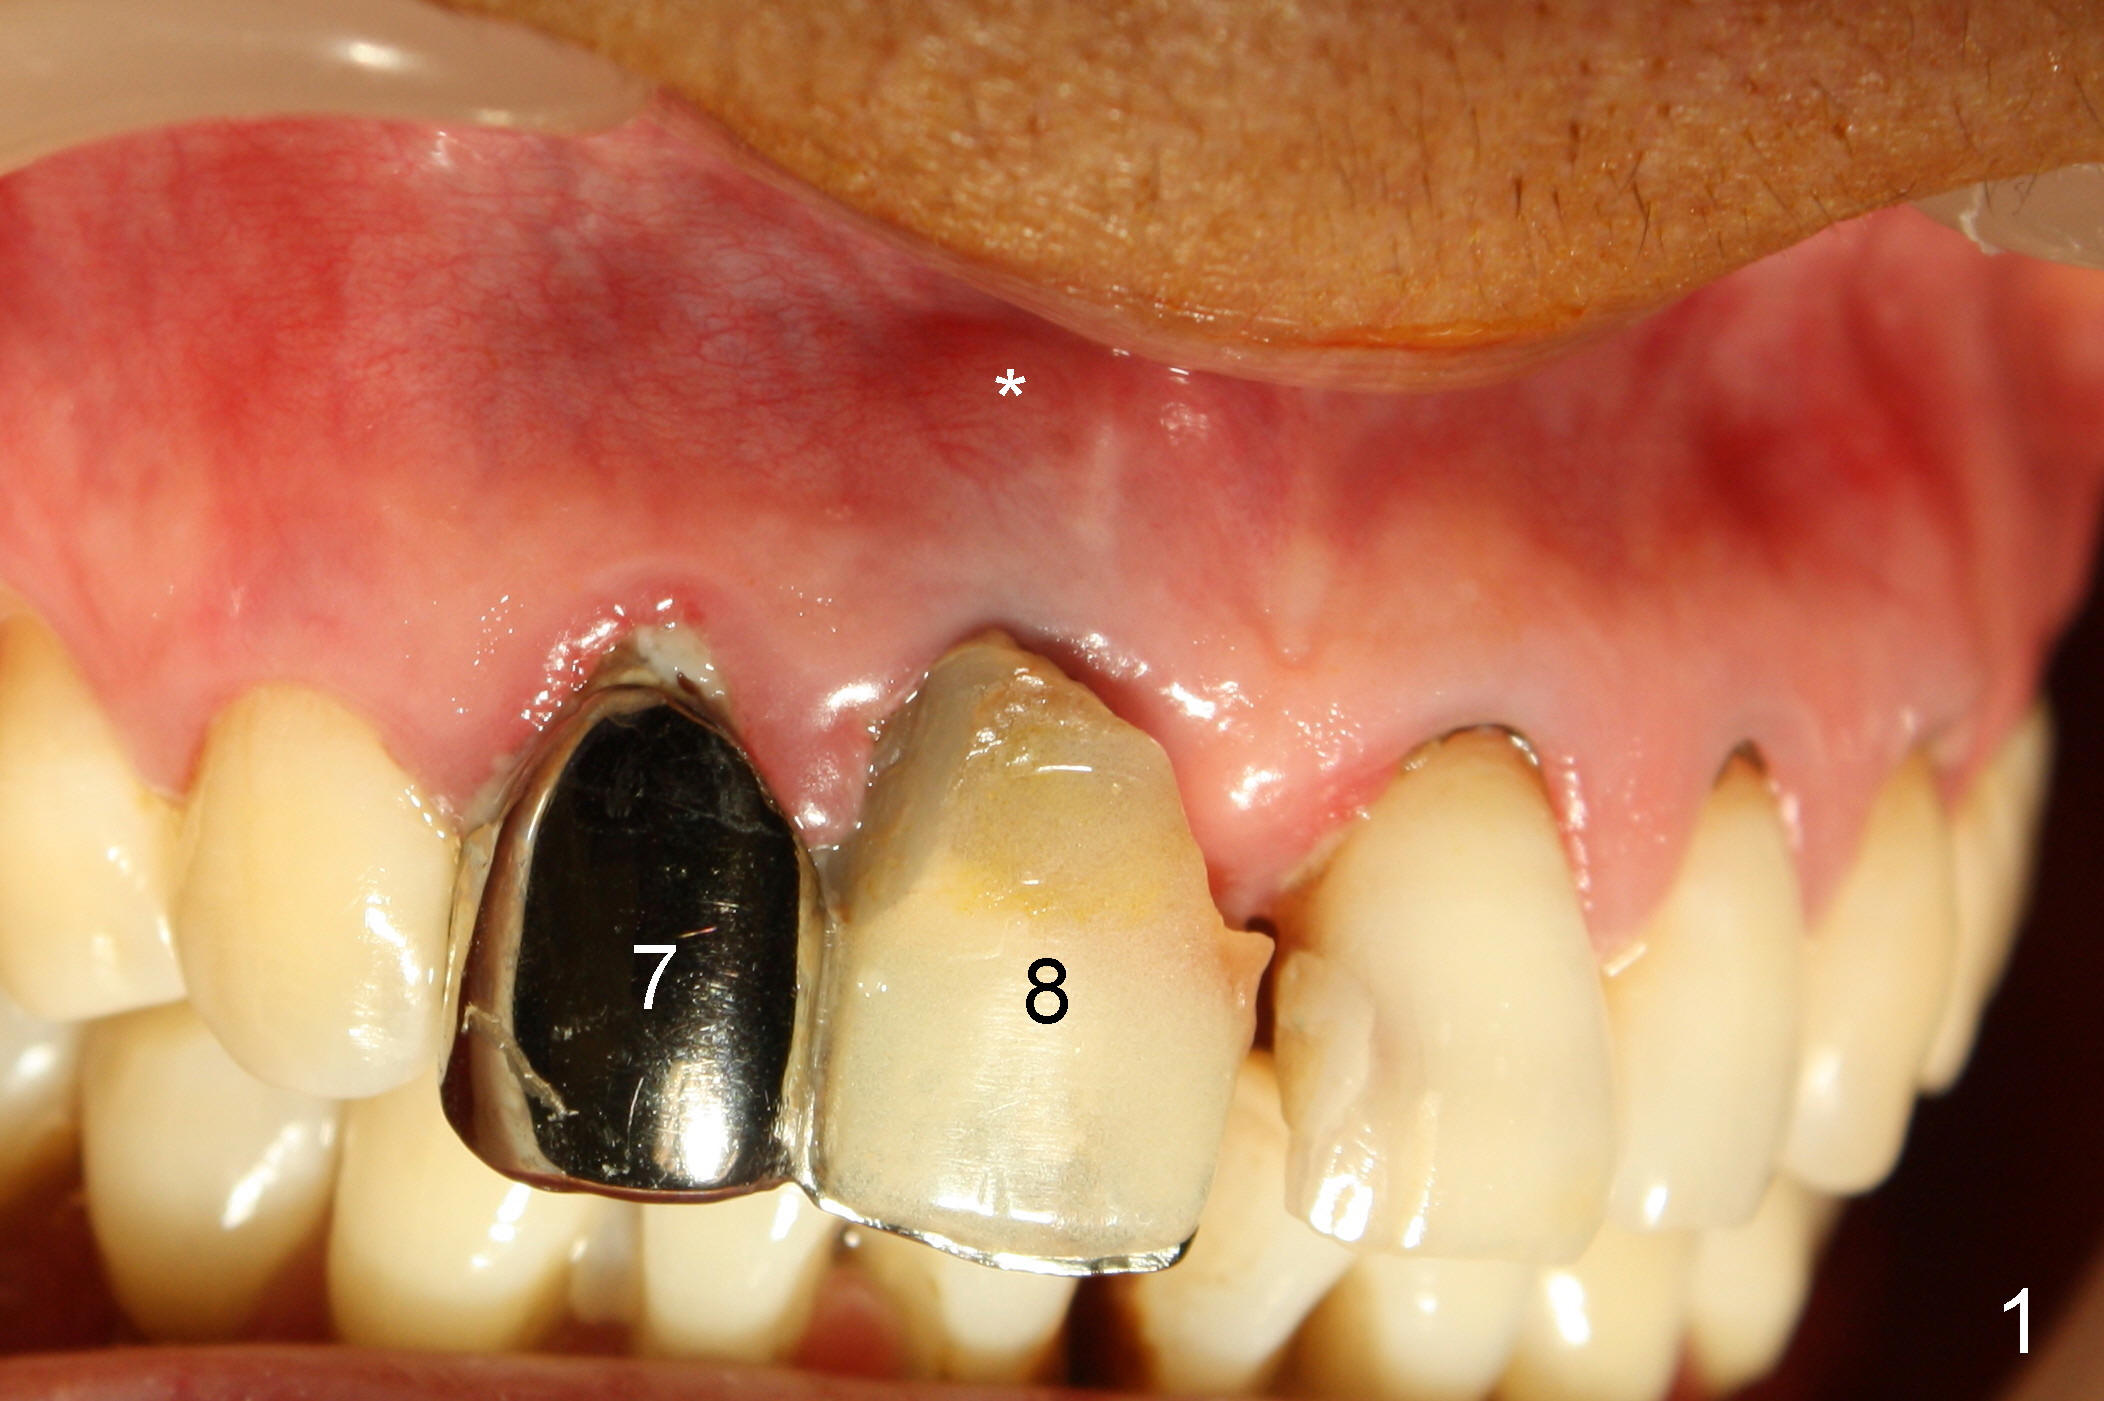

A 64-year-old lady requests replacing #7 and 8 crowns (Fig.1,2). When #8 is extracted, the labial plate is found to be missing (Fig.3). Following 2 mm pilot drill (Fig.4,5 P), 3.8 mm tap drill (Fig.6,7 T) and 4.5x14 mm implant (Fig.8 I) and 4.8 mm abutment (Fig.9 A), corticocancellous bone is harvested from the left tuberosity and placed in the labial gap of the socket (Fig.10 G). Collagen dressing is placed over the bone graft (Fig.11 C). The former is secured in place by an immediate provisional (P).